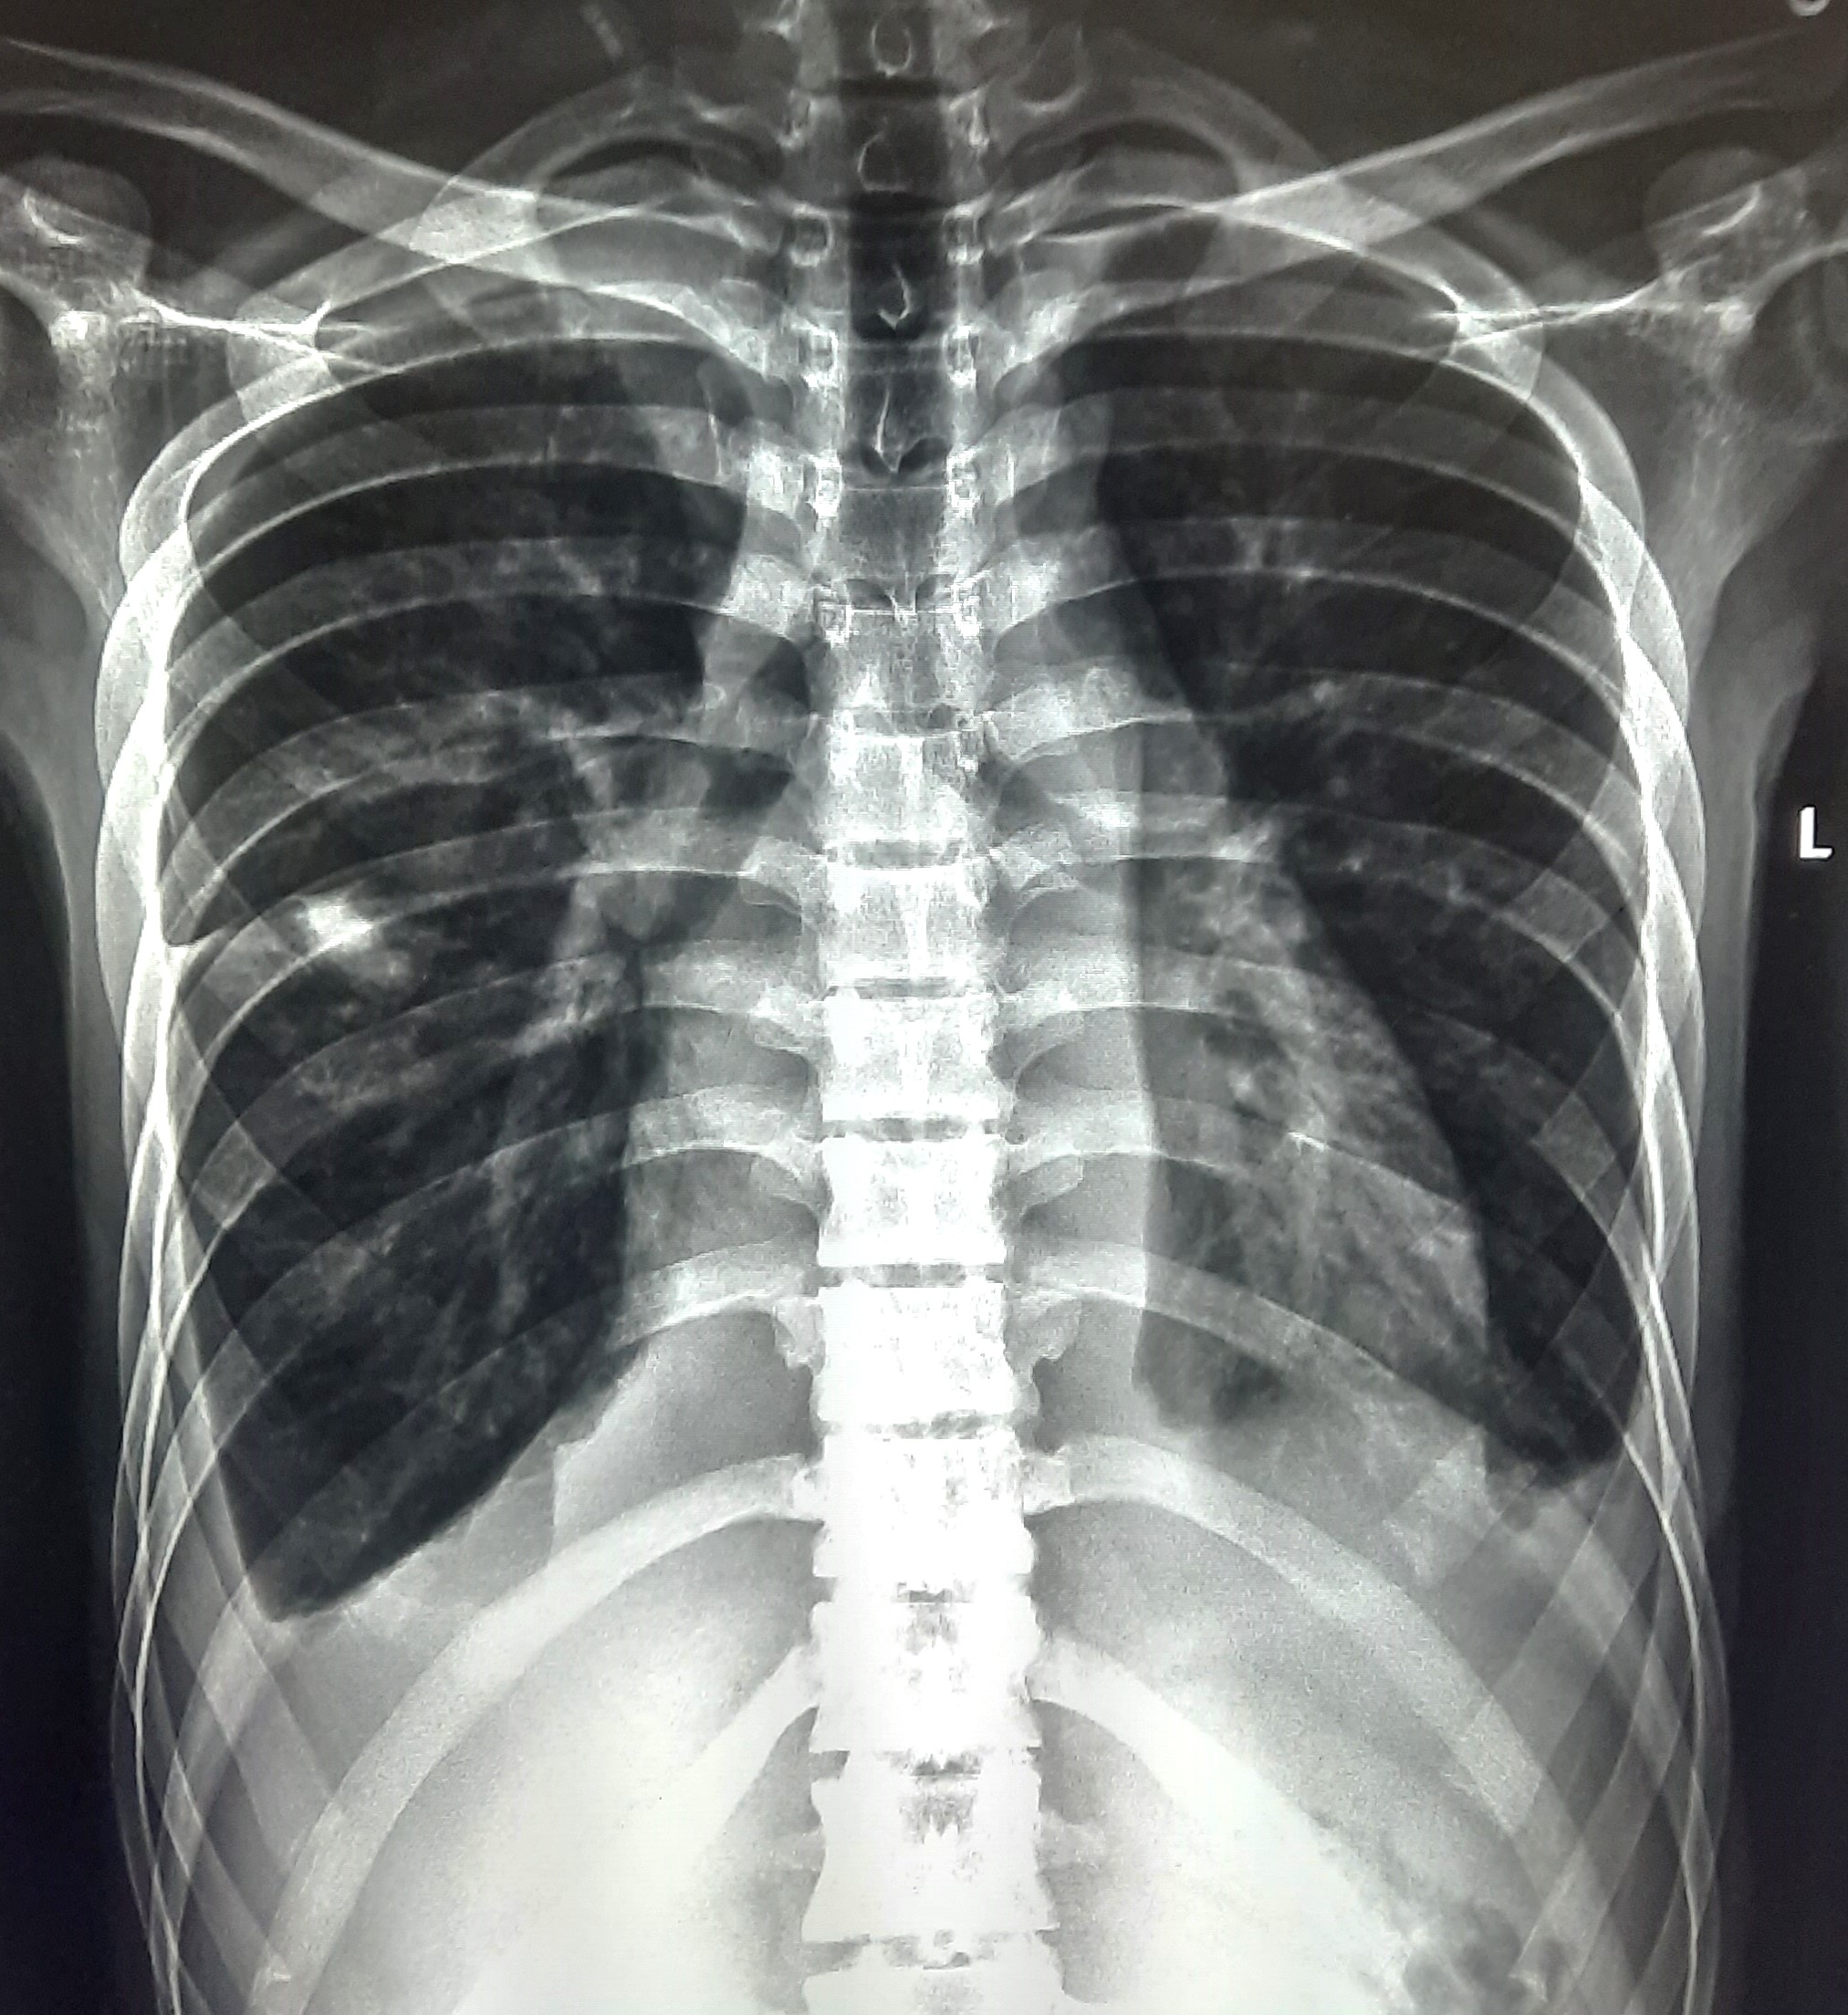

| 52 | IGGMC, Nagpur, Nagpur | P2 | 29-4420 | Hamida Bano | Consent taken on Paper | 56 Yrs. |

Provisional Diag : Post TB Sequelae With Reactivation?

Final Diag : Post TB Sequelae |

Post TB Sequelae | Tracheal Pull Left Side, Left Mid Zone & Upper Zone Fibro cavitary Lesion Present, Compensatory Right lung Hyper Infiltration Present, Few ill-defined Bilateral Lung Opacity Presnt | Abnormality visible on x-ray |